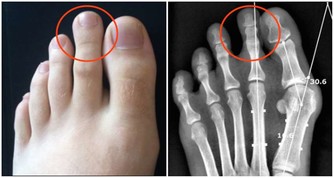

尤其是蹲下去再站起來,對關節的磨損最大。關節軟骨大概有1到2毫米,作用就是緩衝壓力,保護骨骼不破裂。

在爬山和爬樓梯的時候,膝關節會承受超過本身體重3到4倍的壓力。

尤其是50歲以後,人的膝關節多少都會有些磨損的情況,此時,就要減少此類運動。

對於有些有過膝關節損傷的朋友40歲以後就要特別注意了。